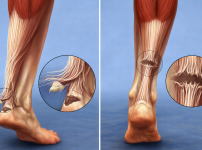

아킬레스건 파열 수술, 다시 운동 가능할까? 강동역 정형외과 치료 및 재활 가이드

1. 운동 중 갑자기 발생할 수 있는 아킬레스건 파열 운동 중 갑자기 뒤꿈치에서 툭 끊어지는 느낌과 함께 극심한 통증이 느껴졌다면 아킬레스건 파열을 의심해야 합…